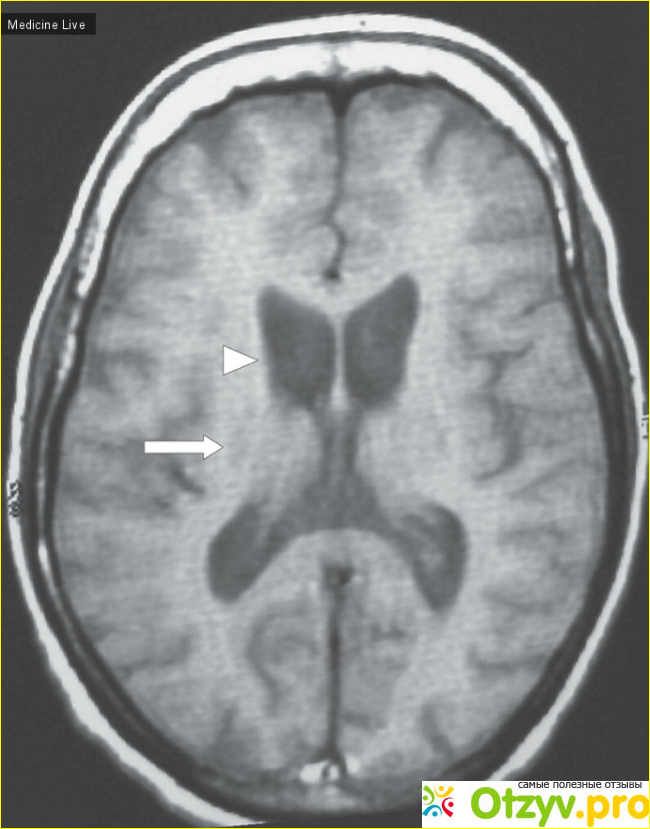

При тщательной диагностики врачи также используют КТ, МРТ, рентген, УЗИ и прочие методы для диагностики.